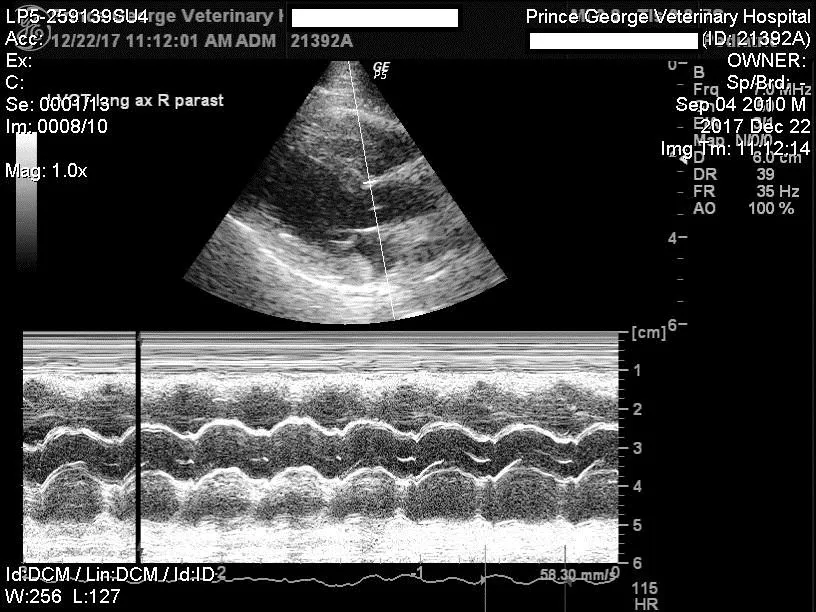

Echocardiography uses ultrasound to obtain images of the heart. This way we can not only assess the size of the heart and its various chambers, but also evaluate the heart muscle, the function of the heart muscle and the condition of the valves in the heart.

Using something called 'Doppler' we can also assess the pattern of blood flow and the speed of blood flow throug the various valves in the heart.